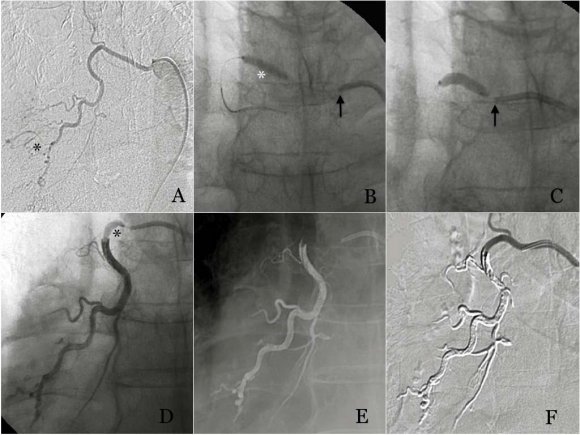

From 2009 to 2014 31 cases were obtained with the inclusion criteria mentioned, of whom 54.8 % were women and 45.2 % were men with a median age of 57 years (range 36 to 84 years); all with a study of abdominal computed tomography. The organs affected by GIST were 51.6 % (16) stomach, 22.6 % (7) jejunum, 12.9 % (4) rectum, 6.5 % (2) duodenum, 3.2 % (1) peritoneum and 3.2 % (1) retroperitoneum (Table 2). 32.3 % (10) of the patients were surgically treated before starting with Imatinib. 67.7 % received first-line molecular targeted therapy with Imatinib, and 32.3 % received second line with Sunitinib. We assessed the response to treatment with a CT scan in an average of 1 to 24 months. According to the criteria of CHOI, we observed 45.2 % (14) complete response, 19.4 (5) stable disease, 19.4 (6) partial response and 16.1 % (5) disease progression (Table 3) Figures 1,2, 3. During that time, metastatic activity was observed in 14 patients representing a 45.1 %, with predominant involvement in the liver with a percentage of 35.5 % of the total (Table 4) Figure 4.